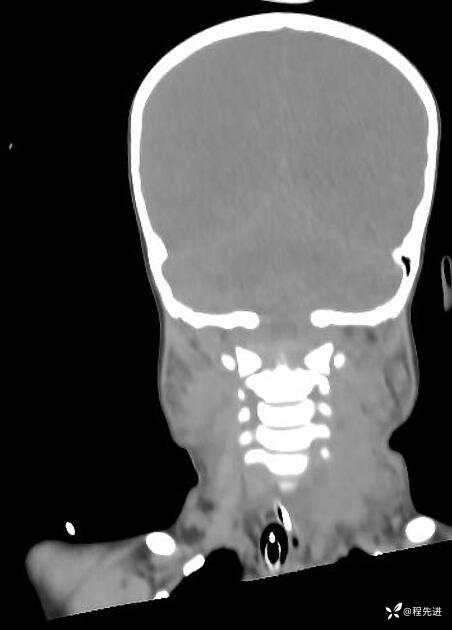

患者性别:男

患者年龄:5岁

简要病史:超速车祸外伤半小时

急诊CT平扫: